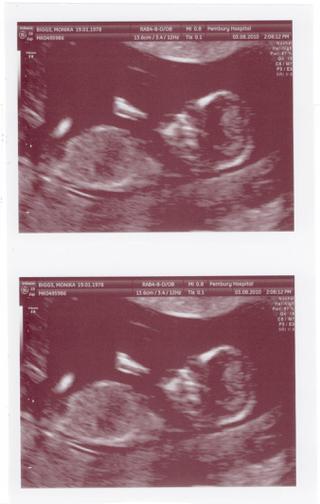

@cutce je kraaasne 😵 ja ked som ho prvy krat videla na sone, tak mi vybehli slzicky, vobec som s tym neratala

@cutce krasne fotky 🙂

..tak to je super, ze ho pozerali tak podrobne 😉 mne sa to zdalo velmi narychlo, manzel sa pytal ake je dlhe, kde ma pupocnik a podobne..ona sama moc nehovorila, az potom nam ukazala hlavicku, nostek a siju..aaale hlavne, ze mse v poriadku 😵